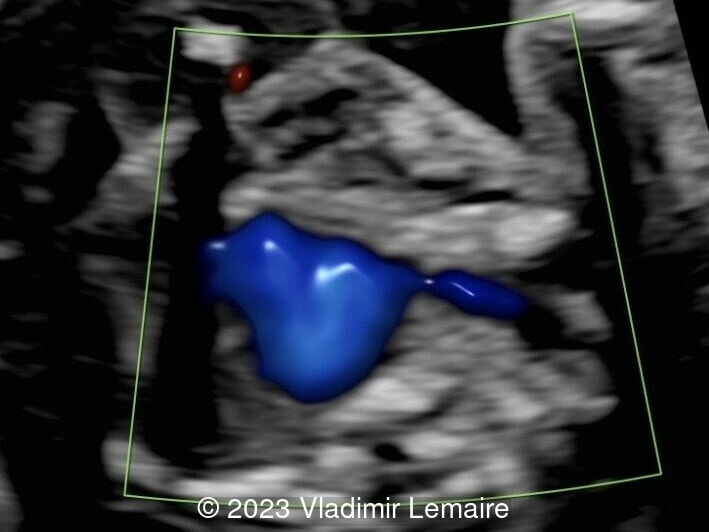

Aberrant right subclavian artery, seen in blue, in a fetus at 23 weeks of gestation.

Image 7 Aberrant right subclavian artery, seen in blue, in a fetus at 23 weeks of gestation.